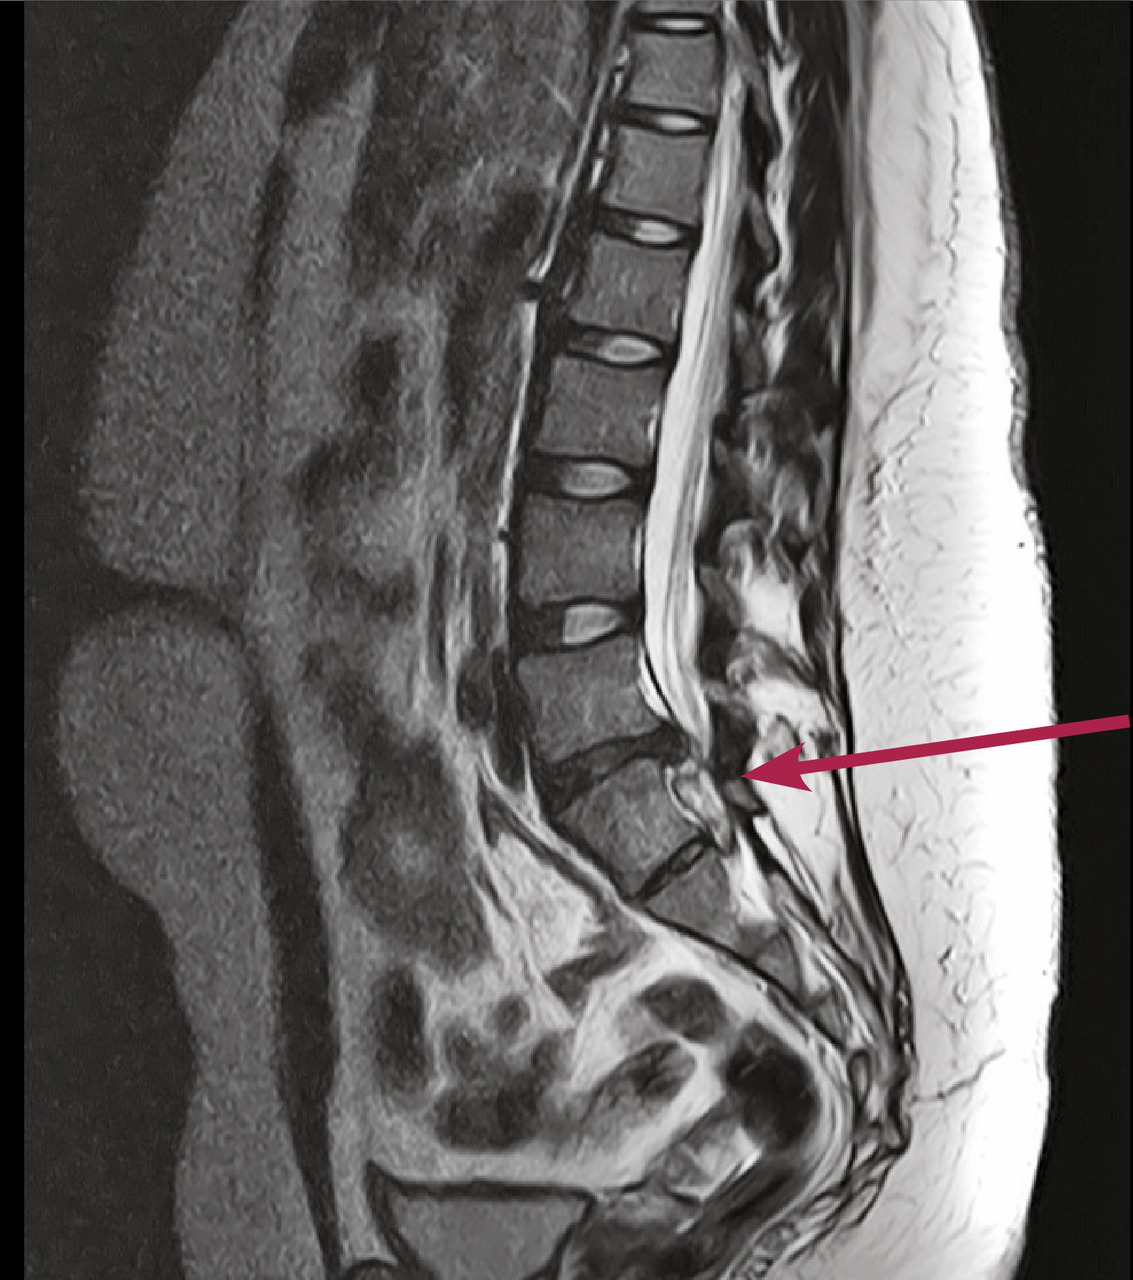

IRM :

– prend peu à peu le pas sur la TDM ;

– analyse plus fine des structures tissulaires, de l’œdème osseux, du sac dural et des racines ;

– coupes sagittales remontant à la charnière thoraco-lombaire : vision plus systématique de l’ensemble de la colonne thoraco-lombaire, lombaire et sacrée ;

– injection de gadolinium : très utile – mais non systématique – pour explorer certaines structures tissulaires (distinction d’une hernie discale d’un tissu cicatriciel postopératoire, d’un neurinome...).